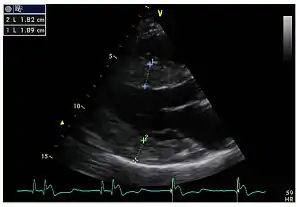

![]() Виражена гіпертрофія лівого шлуночка Виражена гіпертрофія лівого шлуночка | |

Ехокардіографія — основний метод діагностики гіпертрофії міокарда лівого шлуночка.

Ехокардіографічне обстеження дозволяє виміряти товщину стінок серця та розміри лівого шлуночка, на основі яких розраховують:

- масу міокарда лівого шлуночка

- індекс маси міокарда лівого шлуночка

- відносну товщину стінок лівого шлуночка